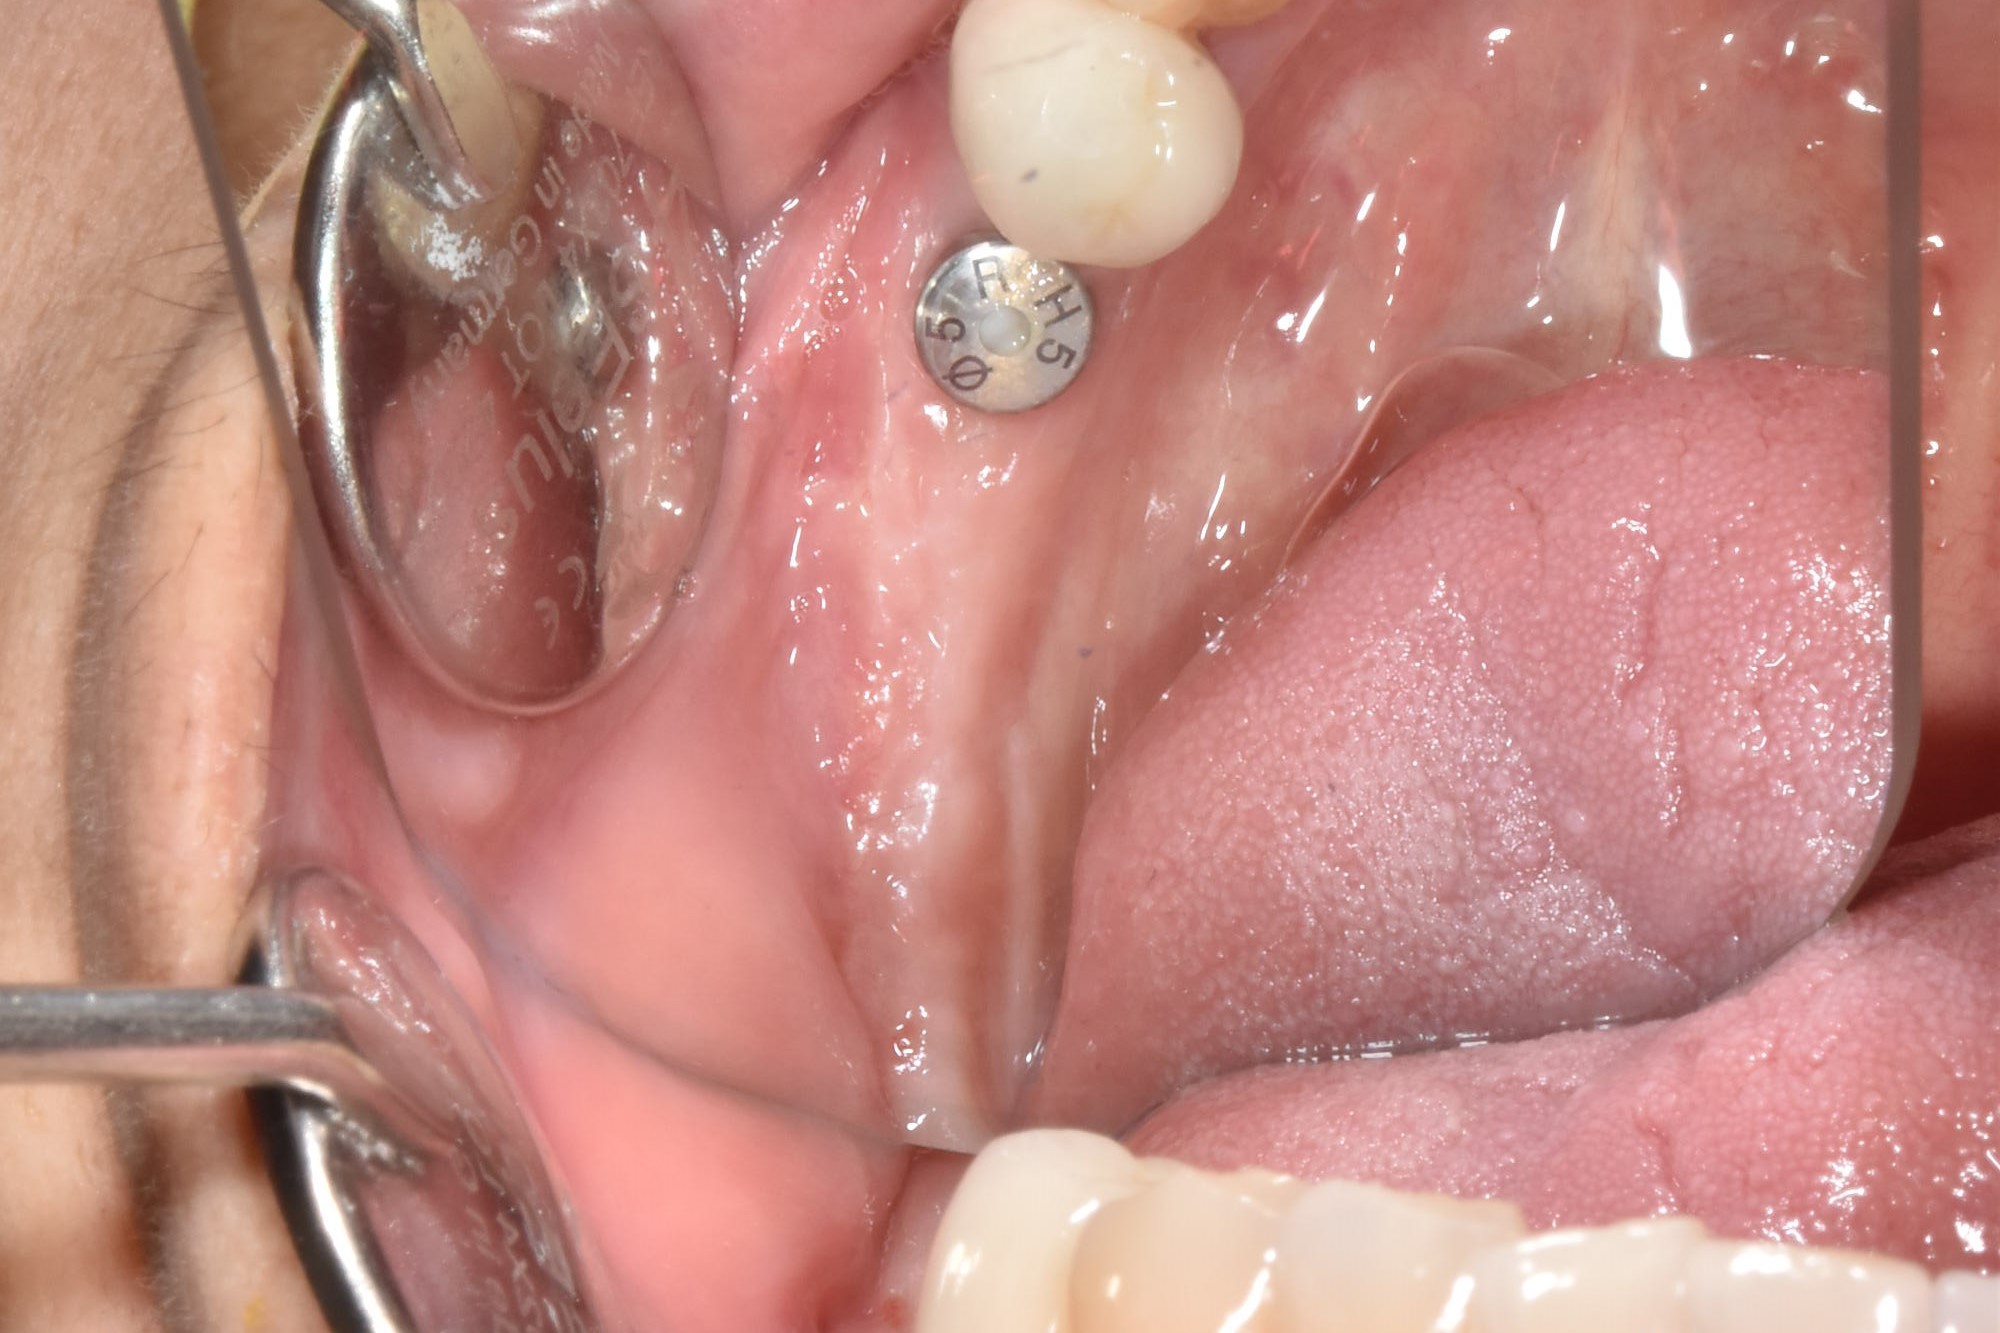

牙齦移植術(補肉)

手術案例

術前加術後案例

案例三